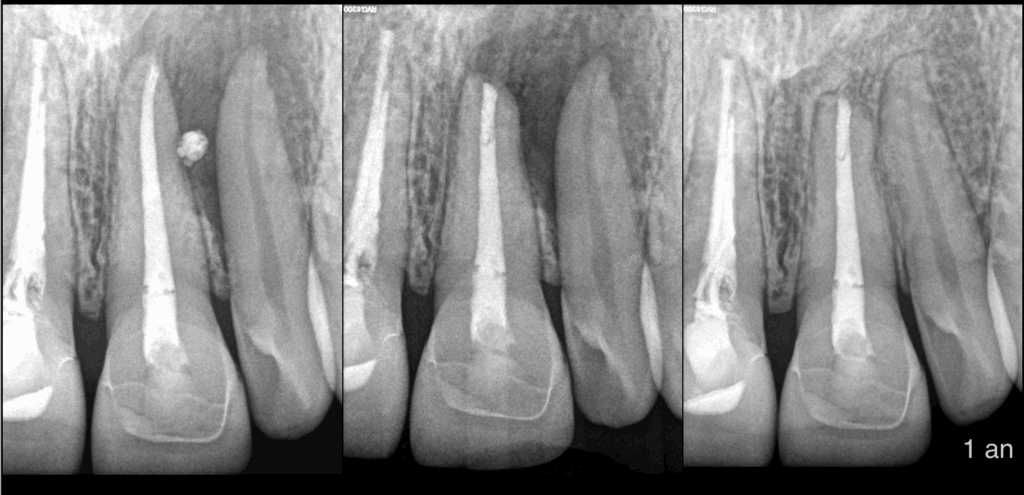

Voici 5 𝐩𝐨𝐢𝐧𝐭𝐬 𝐚̀ 𝐫𝐞𝐭𝐞𝐧𝐢𝐫 concernant la chirurgie endodontique de cette 𝟐𝟏 :

1️⃣ Un 𝐭𝐫𝐚𝐢𝐭𝐞𝐦𝐞𝐧𝐭 𝐜𝐚𝐧𝐚𝐥𝐚𝐢𝐫𝐞 répondant aux 𝐜𝐫𝐢𝐭𝐞̀𝐫𝐞𝐬 𝐝𝐞 𝐪𝐮𝐚𝐥𝐢𝐭𝐞́ n’est pas forcément synonyme d’𝐞𝐟𝐟𝐢𝐜𝐚𝐜𝐢𝐭𝐞́ 𝐝𝐮 𝐩𝐨𝐢𝐧𝐭 𝐝𝐞 𝐯𝐮𝐞 𝐨𝐬𝐬𝐞𝐮𝐱 → la 21

2️⃣ Un traitement canalaire ne répondant pas strictement aux critères de qualité peut malgré tout être efficace du point de vue osseux → la 11

3️⃣ Ce n’est pas parce que le traitement canalaire ne répond pas strictement aux critères de qualité que nous allons intervenir au niveau de la 11 au cours de la 𝐦𝐢𝐜𝐫𝐨𝐜𝐡𝐢𝐫𝐮𝐫𝐠𝐢𝐞 𝐞𝐧𝐝𝐨𝐝𝐨𝐧𝐭𝐢𝐪𝐮𝐞 21

4️⃣ Une 𝐥𝐞́𝐬𝐢𝐨𝐧 𝐚𝐩𝐢𝐜𝐚𝐥𝐞 englobant plusieurs dents ? On teste la 𝐬𝐞𝐧𝐬𝐢𝐛𝐢𝐥𝐢𝐭𝐞́ 𝐩𝐮𝐥𝐩𝐚𝐢𝐫𝐞 des dents englobées ! → la 22

5️⃣ On prévient le patient qu’avec la microchirurgie endodontique de la 21, la sensibilité pulpaire de la 22 sera à surveiller et qu’en cas de 𝐧𝐞́𝐜𝐫𝐨𝐬𝐞 𝐩𝐮𝐥𝐩𝐚𝐢𝐫𝐞 le traitement canalaire pourrait être indiqué.